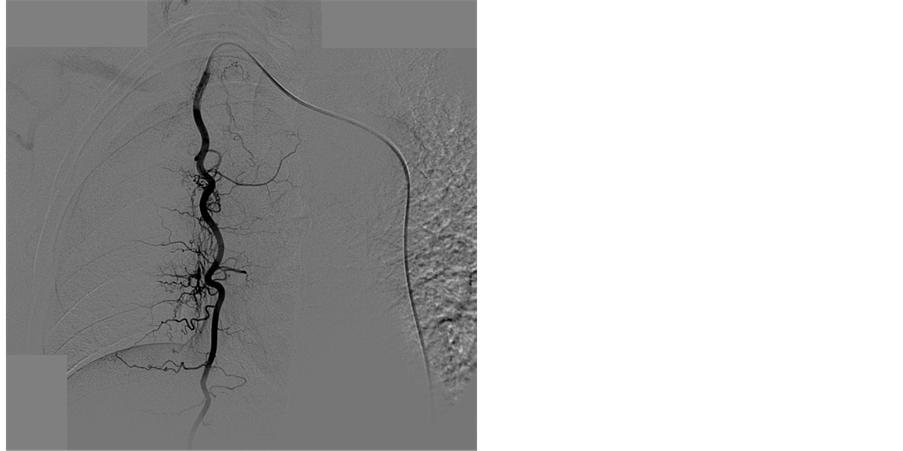

Thirty-eight bronchial arteries and 10 nonbronchial systemic arteries (8 intercostal arteries (Figure 4), one from left subclavian artery and one right internal mammary artery), were found to be responsible for hemoptysis.

Figure 4. (a) MIP CT image in coronal plane shows multiple hypertrophied tortuous right intercostals arteries (b, c) Selective arteriograms showing two hypertrophied tortuous right intercostals arteries.